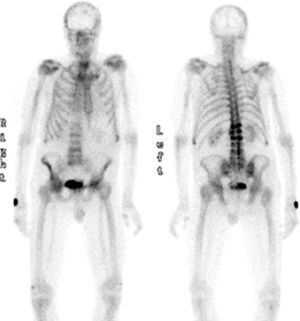

The PSA level was 4ng/mL, and the TSH level 1.56mIU/mL. A bone metabolism study revealed low vitamin D levels (25OHD D, 8.2ng/mL) with an iPTH level of 21pg/mL (NV, 15–65pg/mL). A complete blood count showed normocytic normochromic anemia, as well as leukopenia (3.870 WBCs). The erythrocyte sedimentation rate was 27mm. X-rays of the thoracic spine and the lumbar spine showed multiple vertebral fractures at T12 (grade 3), L1, L2, and L4 (grade 2). Bone densitometry showed a lumbar T score of −1.9 SD, −2.7 SD in total hip, and −0.6 SD in femoral neck, and bone scintigraphy revealed high uptake in T12, L1, L2, and L4 (Fig. 1).

During the study, the patient spontaneously reported pain and functional impotence in the left lower limb. Radiographic study was therefore completed, showing a previously unknown hip fracture and multiple lytic lesions in both femoral shafts (Fig. 2). The patient's course was complicated by respiratory tract infection and severe respiratory failure that did not respond to treatment and eventually caused death. Bone marrow puncture could not be performed.